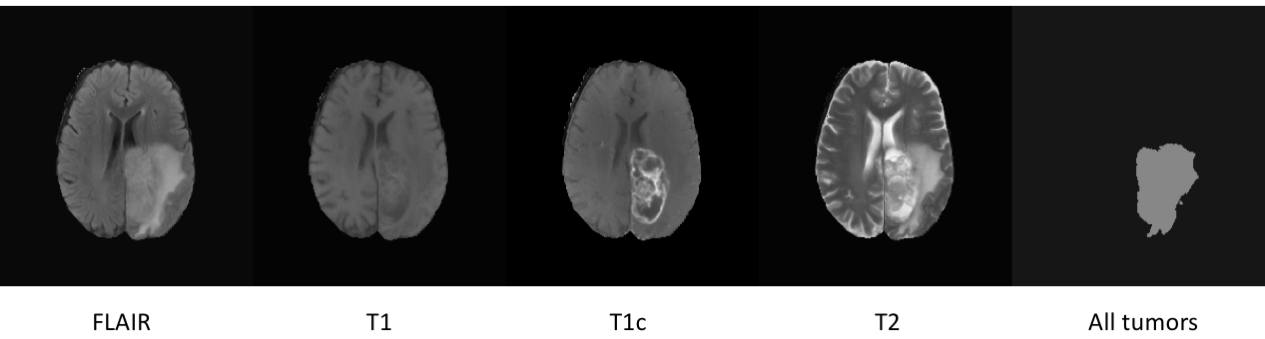

图1:脑部图像

- 每个体积包含4张扫描图像:FLAIR、T1、T1c和T2。

- 每个体积包含4个分割标签:

标签0:背景

标签1:坏死和非增强肿瘤

标签2:水肿

标签4:增强肿瘤